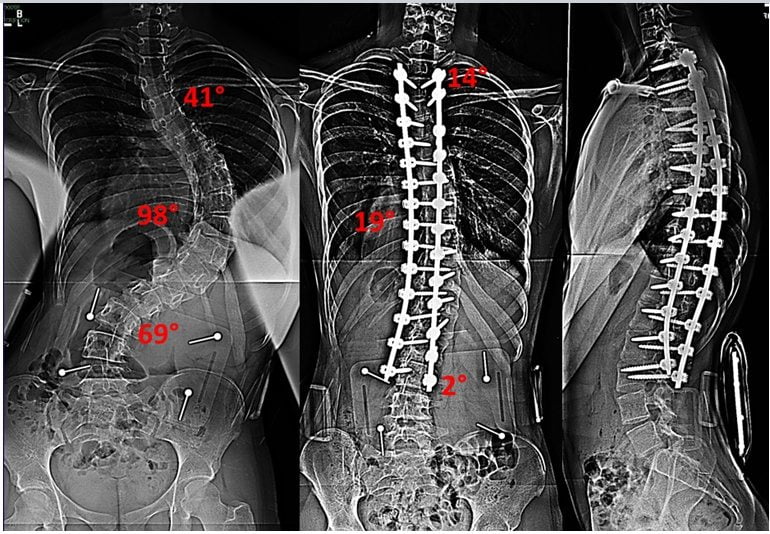

IV степень

При заболевании 4 степени тяжести позвоночный столб искривлен под углом более 50 градусов. Выраженность всех перечисленных клинических проявлений существенно повышена. Реберные горб становится более крупным, в зоне вогнутости сильнее западают ребра. Отмечается значительное компенсаторное растяжение скелетной мускулатуры позвоночника.

Помимо внешнего осмотра пациента, результатов ряда функциональных тестов, в диагностике сколиоза наиболее информативна рентгенография. Сначала исследование проводится в положении стоя, затем — лежа при умеренном растягивании для более детальной оценки искривления позвоночника.

Рассчитать угол сколиотической дуги помогает методика, разработанная Коббом. Сначала на рентгенографическое изображение, сделанное в прямой проекции, наносятся две линии параллельно замыкательным пластинкам здоровых позвонков, а потом измеряется угол между ними.

Хирургическое лечение

При проведении операции позвоночник выпрямляется с помощью специальных металлических конструкций, а пораженный отдел обездвиживается. Фиксация выполняется пластинами, стержнями, крючками, винтами. Чтобы расширить позвонки, придать позвоночному столбу правильную форму, хирурги используют костные трансплантаты. В зависимости от тяжести сколиоза, его локализации операция проводится трансторакально, дорсально или методом торакофренолюмботомии.